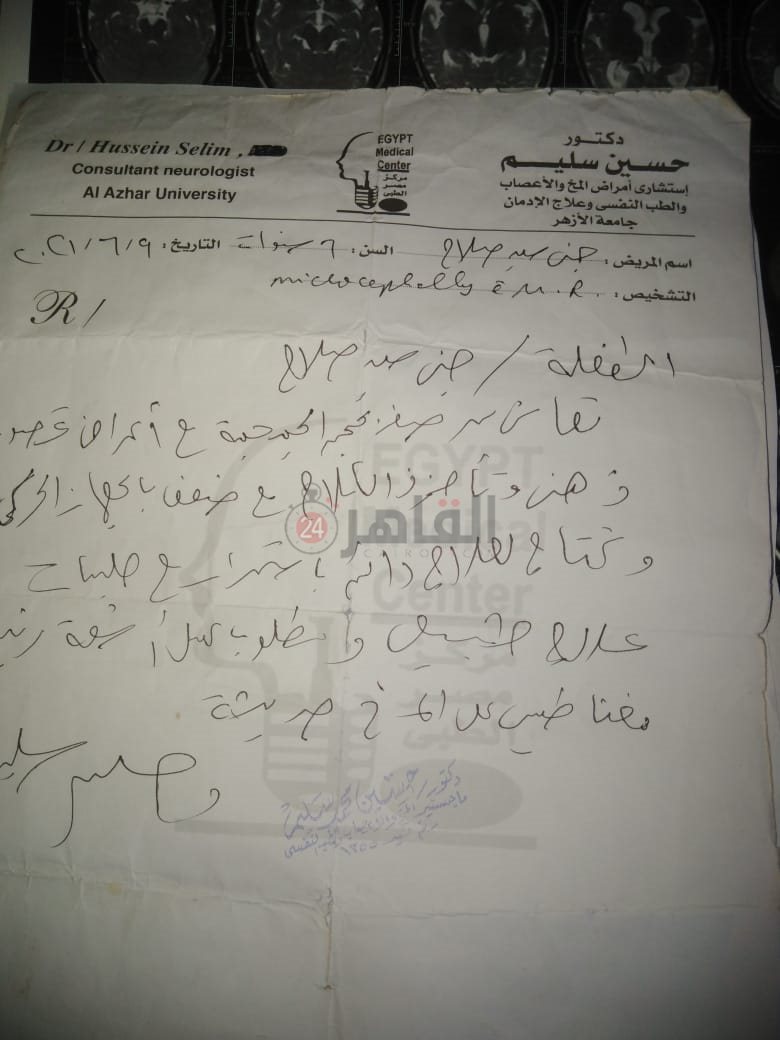

من جانبه، قال صلاح سيد، والد الطفلة جنى صلاح، إن ابنته تعاني من ضمور في المخ منذ ولادتها، نتيجة خطأ طبي، أدى إلى نقص كبير في الأكسجين لديها.

وأضاف في تصريحات خاصة لـ "القاهرة 24": "جنى تبلغ من العمر 6 سنوات، لا تستطيع المشي أو الوقوف على قدميها، نتيجة إصابتها بضمور في المخ منذ ولادتها".

وتابع: "مكنتش بتتحرك خالص، وجسمها طري، روحت كشفت عليها، وعملت أشعة وتحاليل كتير، أتأكدنا إصابتها بضمور في المخ"، مضيفًا:" مش بتعرف تأكل احنا اللي بنأكلها، هي عقلها كويس لكن مش بتتحرك ولا تتكلم".

وأوضح أن الطبيب الخاص بها أكد أن هناك داء خارج مصر يحسن من حالتها، ولكن باهظ الثمن، وتحتاج تناوله بشكل دوري.

واستكمل:" حاليًا تتناول أدوية شرب عادية، لحين توفيرالدولة علاجها من خارج مصر"، مشيرًا: "مفعتش قضية على الدكتور، ورضيت بقضاء ربنا".